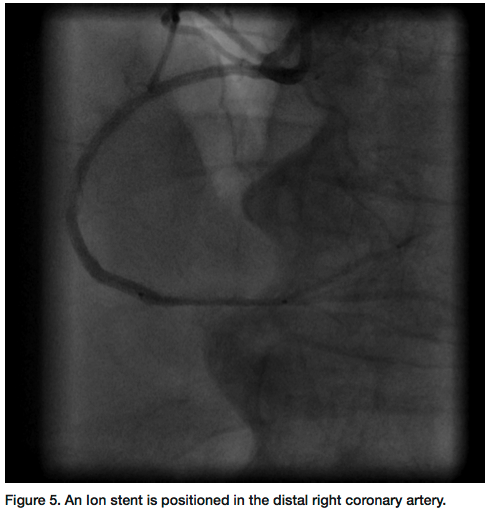

Corporation) was used. The laser softened the cap and allowed us to cross through the entire segment of the CTO with a Kinetix wire. Further lasing was performed at 80 Hertz pulse fluency and at 80 mJ/mm2 repetition cycle for debulking of the entire in-stent occlusion area (Figure 4). A 2.75mm balloon was utilized to pre-dilate the whole length of the CTO. Intravascular ultrasound (IVUS) was performed. Multiple overlapping Ion drug-eluting stents (Boston Scientific) were deployed to the RCA (Figure 5) and post dilated to 3.00 mm, demonstrating excellent angiographic results and TIMI-III flow (Figure 6). The sheath was removed and a hemostatic band was applied for two hours. The patient was discharged the next morning on prasugrel and aspirin along with other medications.